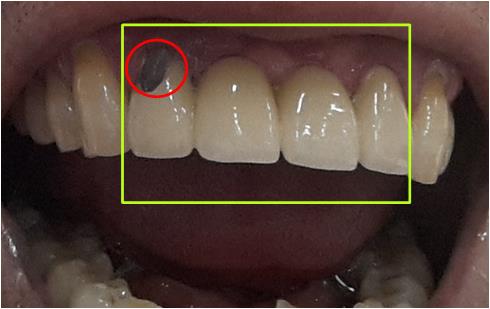

÷ºÎ»çÁøÀº ÀúÀÇ Ä¡¾Æ »çÁøÀÔ´Ï´Ù.

³ë¶õ»ö¾ÈÀÇ °³ Ä¡¾Æ´Â ÀÇÄ¡ÀÔ´Ï´Ù.

2°³ÀÇ Ä¡±ÙÀ» ÀÌ¿ëÇÏ¿© 2°³¸¦ ºê¸´ÁöÇüÀ¸·Î ¿¬°áµÇ¾î ÀÖ½À´Ï´Ù.

Àû»ö¿øÀ¸·Î Ç¥½ÃµÈ ºÎºÐÀº ÀϺΰ¡ 꺠Áø ºÎºÐÀÔ´Ï´Ù.

Ä¡·á°¡ °¡´ÉÇÏ´Ù¸é Ä¡·á¹æ¹ý°ú Ä¡·á½Ã°£, Ä¡·áºñ¿ë¿¡ ´ëÇØ¼

µµ¿òÀ» ¹Þ°íÀÚ ÇÕ´Ï´Ù.